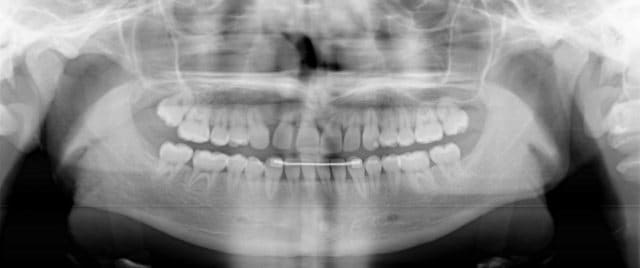

Jeune patiente de 13 ans, après un traitement de 4 années chez un exclusif ODF.

porter un diagnostic de rhyzalyse est un peu court au vu d'une seule pano finale.

1) comparer avec un état initial avant traitement prévaut (référentiel indispensable)

2)vérifier avant et après TT la vestibulo-version (torque)des dents qui laisse en arriere du plan de coupe une partie des apex et offre un faux positif de rhyzalyse

3)observer le rapport couronne/racine de toute les dents et l'harmonie d'ensemble de ce rapport (dents un peu courtes dans le cas présent à mon avis)

4)doute sur 22 (voir pour 12)

5) la position ectopique de 23 me fait penser à ces cas d'endomaxillie du prémaxillaire où on onserve une augmentation du surplomb avec proalvéolie incisive et fausse rhyzalyse

c'est vrai que tout le haut est un peu court,mais l'arrondi des apex incisifs signe souvent la rhizalyse(orthographe officielle)

il faudrait des radios periapicales pour etre sur